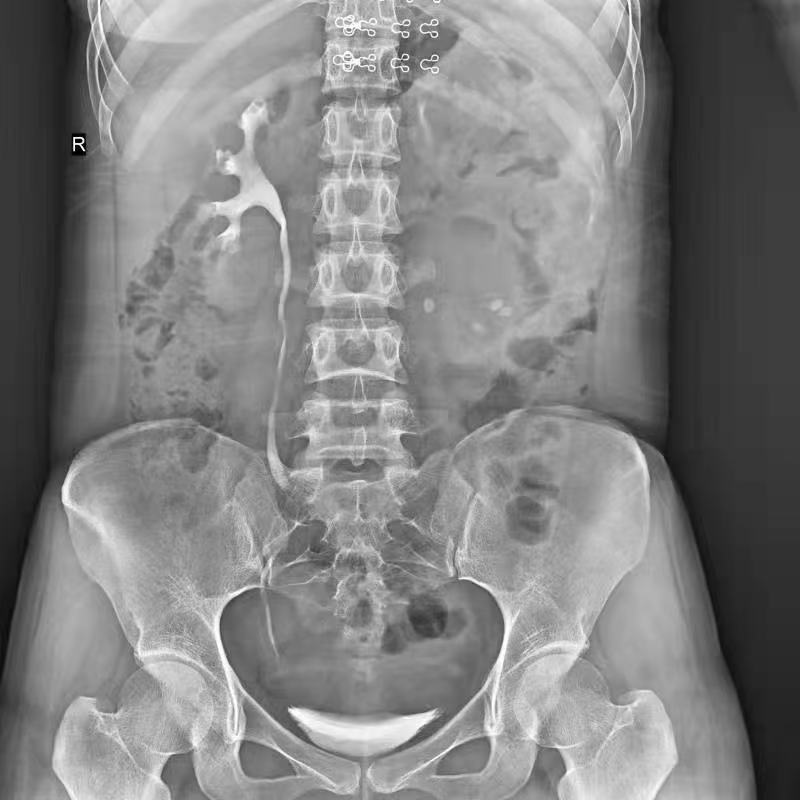

高千伏攝影

盆骨 (2)

腎盂造影